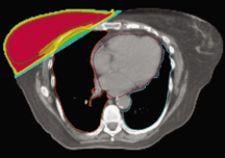

TomoDirect was developed as a complement to helical TomoTherapy, with both modes utilizing the same binary multi-leaf collimator and CT-style gantry technology, and sharing a simple, consistent treatment planning and delivery process. The choice of which modality to use for a given case will depend on the nature of the tumor volume and surrounding organs at risk. TomoDirect allows clinicians to choose several discrete angles as well as the optimal modulation level required for delivery. It is expected to provide significant time savings in both the planning and delivery phases for several clinical scenarios, including whole breast irradiation and palliative treatments. In addition to the added capabilities offered by TomoDirect, the Hi·Art system’s treatment modes are being expanded to include 3D conformal delivery, thereby providing a comprehensive range of options for all clinical cases.